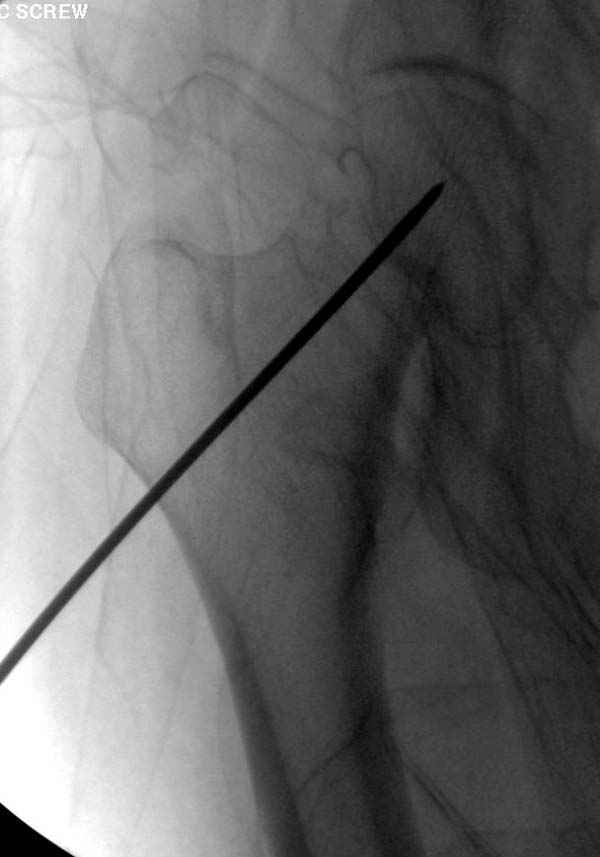

Re: неполный перелом шейки

Профилактику дальнейшего раскола неполного перелома шейки провели тремя канюлированными шурупами.